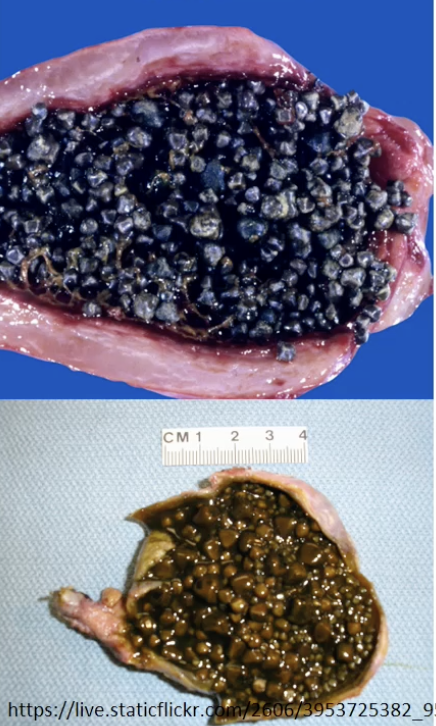

Cholelithiasis =

gallstones

Cholesterol Cholelithiasis

Biliruben-Calcium Cholelithiasis - Brown = infection, e coli, black = Hemolytic Disorders and Malaria